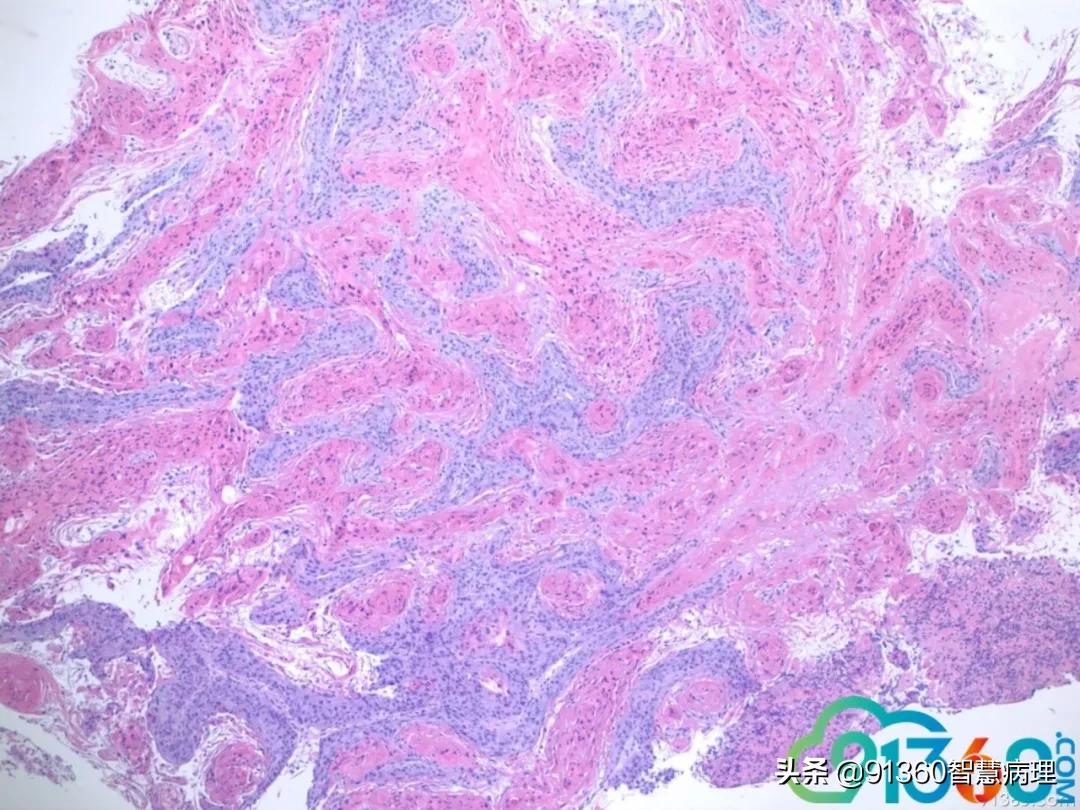

喻明芙 和Pap 符合@赵澄泉UPMC 谢谢 赵澄泉 组织切片有假象,但局部可有明显浸润 喻明芙 这就是Pap中看到的异常角化细胞

喻明芙 @赵澄泉UPMC 先给大家机会看看组织学@赵澄泉UPMC 谢谢分享 赵澄泉 @阎培莎 @诸城市妇幼保健院王瑞辉 群管 @姜锦贵,江苏金湖医院 @喻明芙/病理/康州 @彭振武(广州安必平公司) @厦门motic孙煜昀 @廖新波(JMC-NY) @舒兰市中医院病理科宋晓华 细胞学是atypical parakeratosis cells. 这是为什么大家觉得很难报LSIL, HSIL, cancer, even ascH. 经验:如果这种细胞很多尤其HPV阳,一定要想着鳞癌的可能,一定和临床沟通,组织活检,不要漏掉病人,这例我报的ASCH,备注强调病人需活检。实际工作中组织学对照是学习细胞学最好老师 石丽华 @赵澄泉UPMC 学习了谢谢老师分享这种角化不认识,实际工作中易漏掉 孙煜昀 乳头状的鳞状上皮病变,低级别时也可以出现出现这种细胞形态。两者鉴别主要是坏死和里面混杂高级别细胞,赵老师给的病例细胞学没有明确高级别细胞,报ah可以。但是要打的更高,可能需要更多视野的支持 Andy K (纽约) 这种dyskeratotic cells是高度怀疑鳞癌的

喻明芙 我学习的麟癌有3大特征:肿瘤素质(非常难认),异常角化,和异形麟装上皮有核仁。反过来看,这里Pap缺第三,但要怀疑。我会写到Note 孙煜昀 支持老师看法红圈的细胞对照的很好,绿圈的细胞在细胞学没有对应,只有我打剪头的一个细胞,所以才加大了难度可能在肿瘤表面全是角化不全的细胞。很难取到下面的肿瘤主体